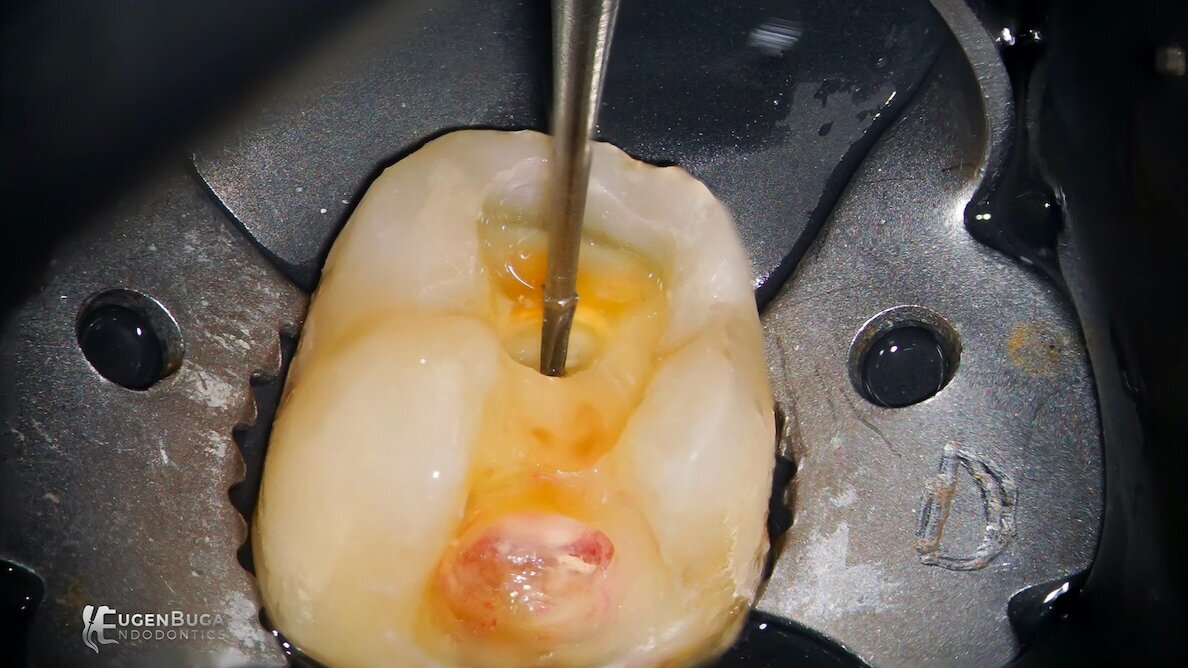

Included in the presentation will be a thorough discussion concerning access preparation, rotary file design, instrumentation techniques and obturation options. (Image: Dr Eugen Buga)

We will talk about all phases of endodontic treatment and cover topics such as how to perform conservative access professionally quickly and efficiently; how to choose the perfect rotary file system, filtering all unnecessary information; and my top three instrumentation protocols for most cases with complex anatomies.